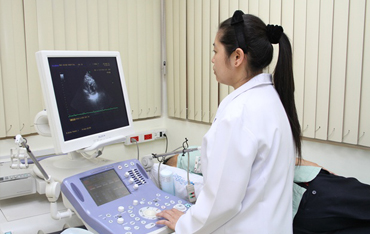

โรงพยาบาลธนบุรี ตรัง มีเครื่องมือแพทย์ที่ทันสมัยและแม่นยำ ในการตรวจวินิจฉัยรักษาของแพทย์ เพื่อความรวดเร็วและปลอดภัยของผู้รับบริการ

เครื่องอัลตร้าซาวด์สี 4 มิติ (ULTRASOUND 4D)